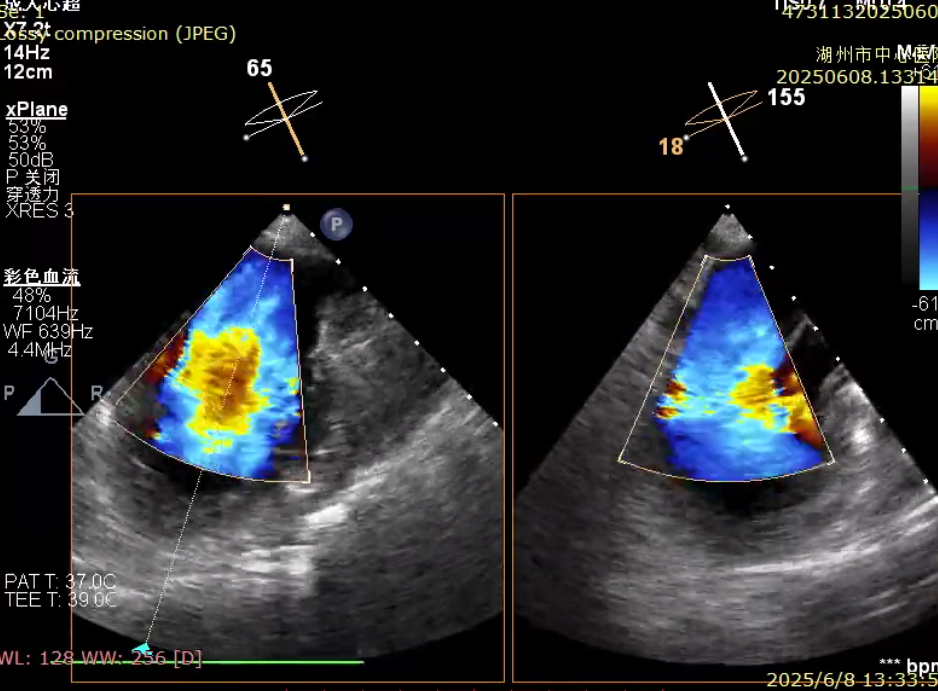

79 岁的李奶奶因活动后胸闷、血压偏低入院,心超提示二尖瓣脱垂伴重度返流,左房压力高达 45 mmHg,常规药物治疗无效。考虑到患者高龄、瘦弱且基础病多,团队选择经导管二尖瓣钳夹术。术中,在超声实时引导下,通过股静脉送入钳夹装置,精准夹合脱垂瓣叶,左房压力即刻降至 12 mmHg。